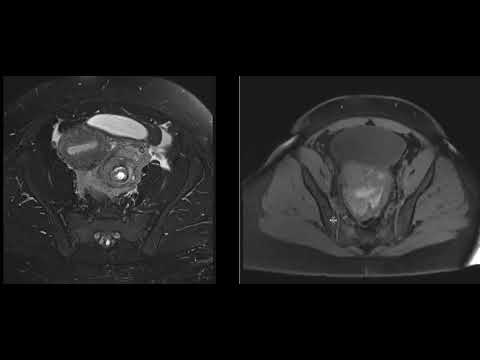

Hellow guys, Welcome to my website, and you are watching Ruptured ECTOPIC pregnancy: A Medical Emergency. and this vIdeo is uploaded by Dr. Elena Rodriguez at 2019-06-30T10:56:34-07:00. We are pramote this video only for entertainment and educational perpose only. So, I hop you like our website.